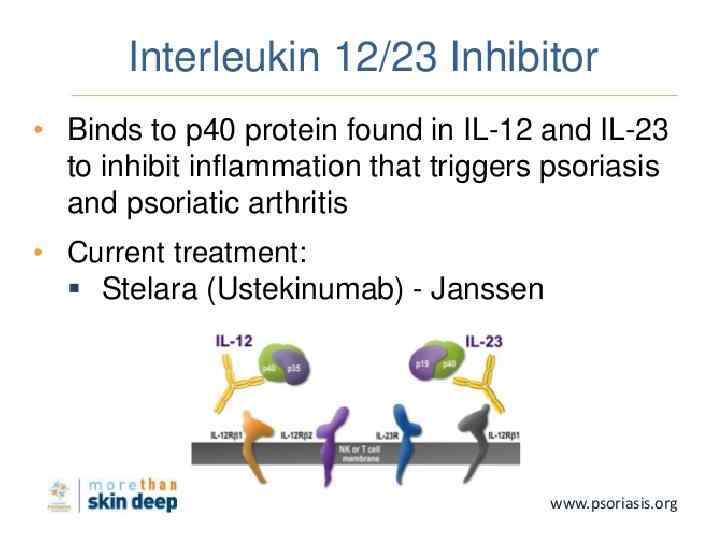

Treatment